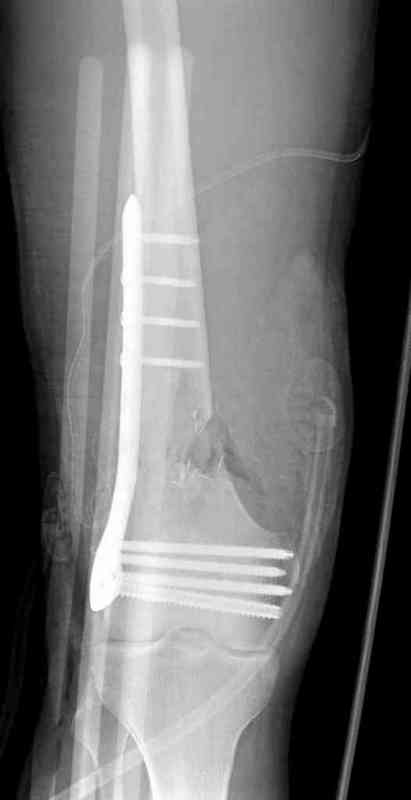

Больная К. с тугим ложным суставом н/3 бедра. Травма в 2005 г.-закрытый перелом, остеосинтез в аппарате Илизарова. В 2006 г. оперирована по поводу несросшегося перелома.

В ноябре 2006 г. демонтаж аппарата, после чего в течении месяца развилась вальгусная деформация. Имеется патологическая подвижность. Объем движений в коленном суставе 180-140. На обсуждение выносятся варианты лечения погружными конструкциями.

The patient with non-union of the distal femur. Trauma in 2005 - closed fracture of the femur, external fixation with Ilizarov apparatus. Non-union. In 2006 open reduction and external fixation with Ilizarov apparatus. In November 2006 the apparatus was removed, after that valgus deformation developed. There is pathological mobility. The knee motion 180-140. We'd like to discuss options of internal fixation.